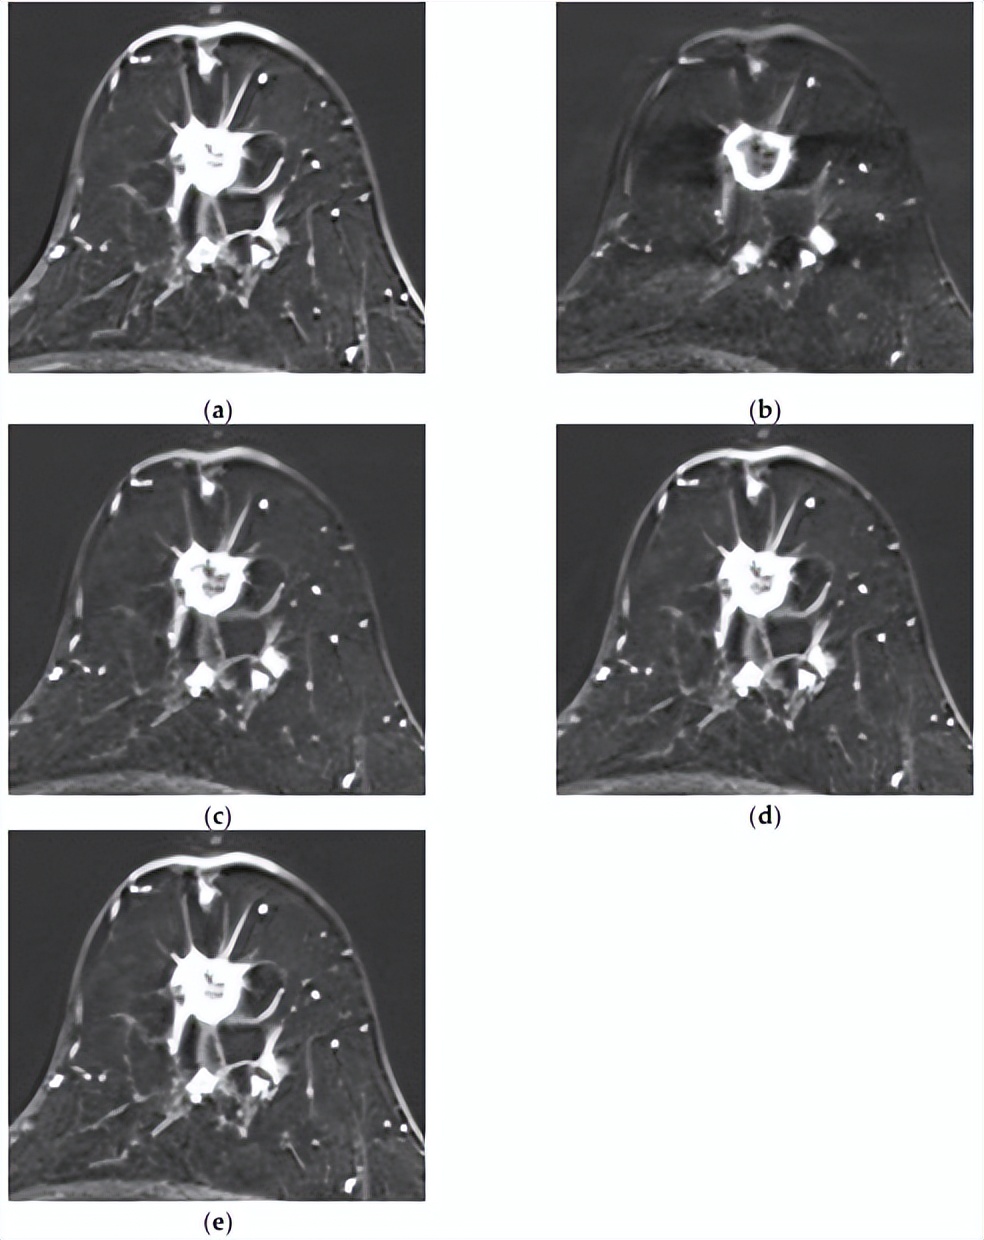

[MRI和组合模型均正确预测了复发。一名50岁女性,具有不均匀致密的纤维腺体组织和中度背景实质强化。注射对比剂后(a)1分钟、(b)2分钟、(c)3分钟、(d)4分钟和(e)5分钟的轴向增强T1加权MR图像显示,左乳房12点位置有一个1.8×1.6厘米的不规则形状、边缘有毛刺、边缘增强的肿块。在主要病变后方可见另一个8毫米增强肿块,侧面还有另外两个8毫米增强肿块,它们似乎相互连接。虽然图像中未显示,但上内象限存在另一个增强病变,证实了多中心疾病。两种模型均成功预测了该复发病例。]